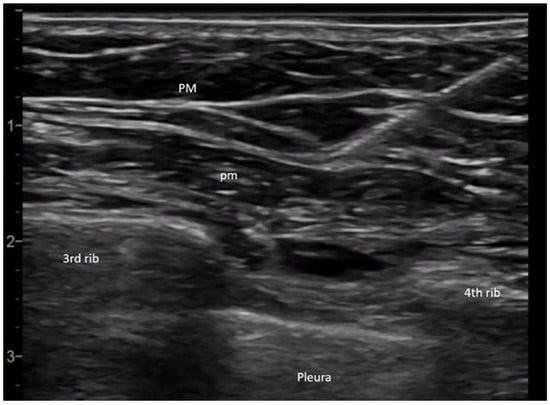

4.2. Anesthetic Procedure for Interpectoral (PECS) Block